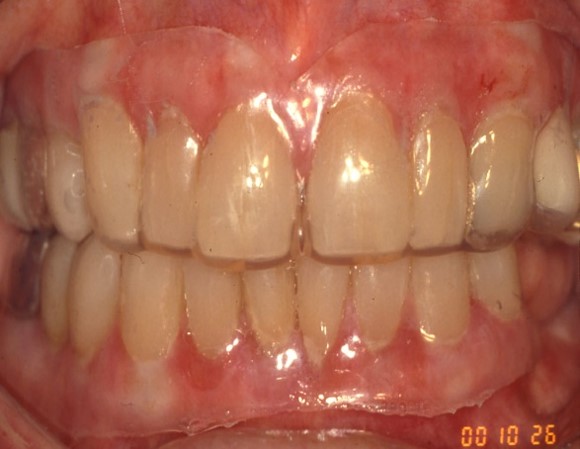

Figure 1 & 2: Lichen planus occurring on the gingiva (desquamative gingivitis) and tongue (plaque-like form).

Figure 3-5: Mucous membrane pemphigoid (MMP) presenting as desquamative gingivitis; poor plaque control resulting from the inability to brush comfortably; patient responded well to topical steroids applied in delivery trays.

Mucous membrane pemphigoid (MMP) is an autoimmune blistering disorder that affects the oral &/or other mucosal surfaces. It affects women twice as often as men and occurs most frequently in the 5th to 7th decades of life.2 Clinically, MMP presents as desquamative gingivitis (bright red gingiva) often showing a positive Nikolsky’s sign (sloughing of the outer surface of the oral mucosa with slight rubbing). (Figures 3-5)